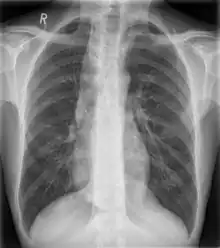

Widened mediastinum

Other namesMediastinal widening

Widened mediastinum in a patient with achalasia

Widened mediastinum/mediastinal widening is where the mediastinum has a width greater than 6 cm on an upright PA chest X-ray or 8 cm on supine AP chest film.[11]

A widened mediastinum can be indicative of several pathologies:[12][13]